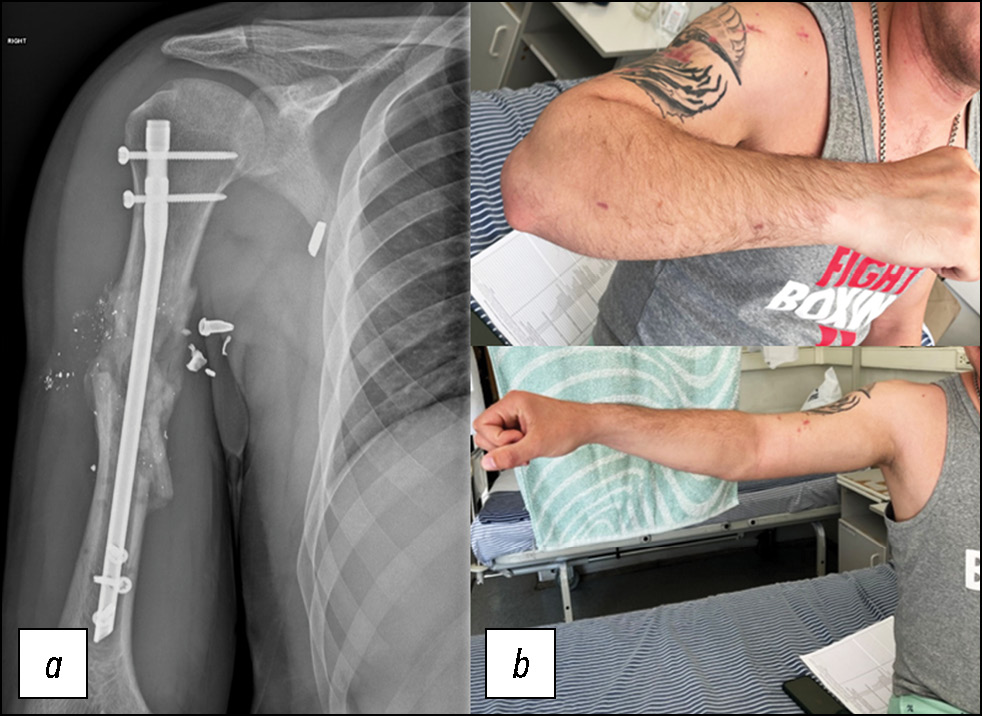

Рис. 4. Пациент 1: a — рентгенограмма после демонтажа аппарата внешней фиксации и внутреннего остеосинтеза проксимальным бедренным штифтом с блокированием, b — внешний вид в первые сутки после операции.

Fig. 4. Patient 1: a, radiograph after removal of the external fixation device and internal osteosynthesis with proximal locking of a femoral nail; b, the patient on the first postoperative day.

Рис. 9. Пациент 2: a — контрольная рентгенограмма спустя 6 месяцев после операции, b — функция верхней конечности после прохождения реабилитационного лечения.

Fig. 9. Patient 2: a, follow-up radiograph six months after surgery; b, upper limb function after rehabilitation.